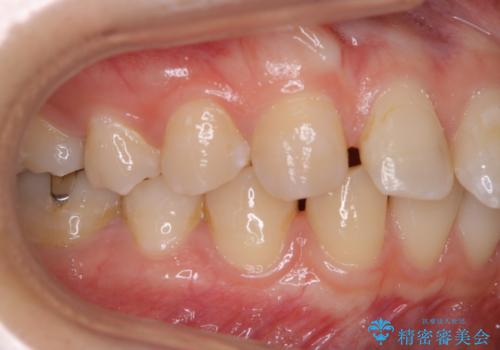

歯並が、がたついている場合はなおさら汚れが溜まりやすいです。矯正治療前や矯正中、定期的にPMTCをすることで、矯正治療中の歯肉トラブルを防ぐことにつながります。